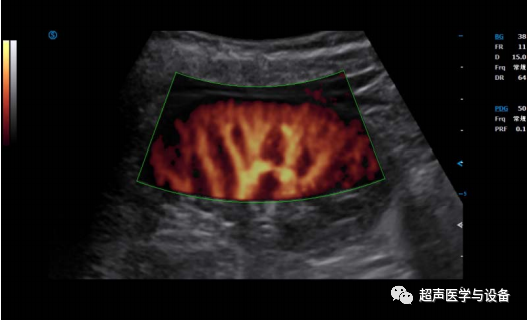

智真光影4D

妇产方面,智真光影4D技术突破更大的三维图像显示区,高效的预备状态裁剪线,通过对光源的控制,让

胎儿更形象生动,栩栩如生。